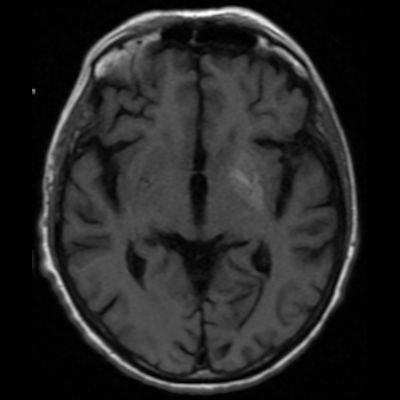

75 yaş, K

Sağ üst kolda atım şeklinde hareket

Tanınız nedir?

Nonketotik hiperglisemik hemikore

Diyabetik striatopati

Non-ketotik hiperglisemiye bağlı hemikore-hemibalizm

non-ketotic hyperglycemic hemichorea